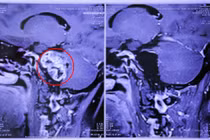

Kết quả chụp MRI cột sống thắt lưng cho thấy một khối u lớn dạng “hình quả tạ” ở vùng L5-S1, xâm lấn nhiều vị trí gồm cơ cạnh sống, cơ psoas (cơ thắt lưng chậu), thân sống, cánh chậu và cả vùng phúc mạc. BS.CKII Lê Điền Sơn, Phó trưởng khoa Ngoại Thần kinh – Bệnh viện Nhân dân 115, chia sẻ:

Hình 1, 2, 3: Ảnh chụp MRI và CT Scan trước phẫu thuật của bệnh nhân L. cho thấy khối u kích thước lớn (hình 2, mũi tên đỏ) xâm lấn các cấu trúc lân cận (hình 2, mũi tên trắng) và gây hủy xương vùng cột sống cùng (hình 3, mũi tên vàng) - Ảnh BVCC